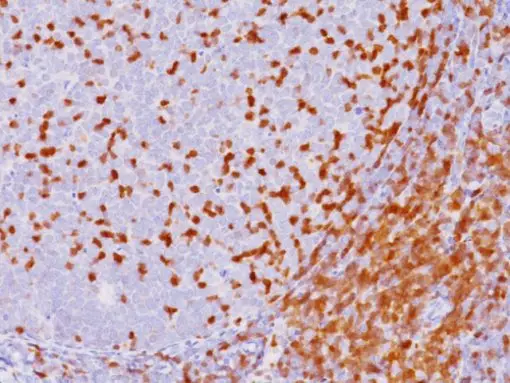

Zeta-associated protein-70 (ZAP-70 antibody) is a tyrosine kinase normally expressed by natural killer cells and T cells. Several studies have indicated a correlation between ZAP-70 expression and immunoglobulin heavy-chain variable-region (IgVH) mutational status in the leukemic cells of chronic lymphocytic leukemia (CLL), with ZAP-70 suggested as a surrogate marker for IgHV mutational status. The mutational status of IgVH genes in CLL is an important prognostic factor in the disease and ZAP-70 overexpression indicates an unfavorable disease course in terms of progression and overall survival.

| LOCALIZATION | Nuclear blush and cytoplasmic |

| POSITIVE CONTROL | Tonsil |